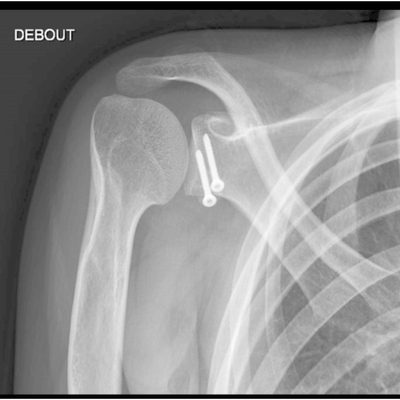

Click on an image below to view more info.